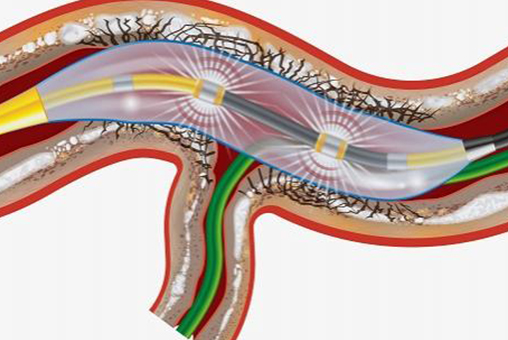

Intravascular Lithotripsy (IVL)

The Shockwave Intravascular Lithotripsy (IVL) System with the Shockwave C2 Coronary Intravascular Lithotripsy (IVL) Catheter consists of the Shockwave C2 Coronary IVL Catheter, IVL Connector Cable, and IVL Generator.